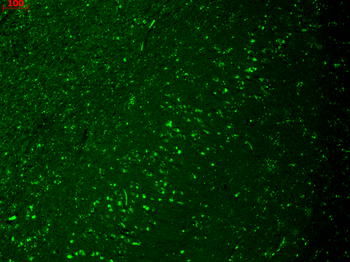

Immunohistochemistry analysis using Mouse Anti-HCN4 Monoclonal Antibody, Clone N114/10. Tissue: hippocampus. Species: Human. Fixation: Bouin's Fixative and paraffin-embedded. Primary Antibody: Mouse Anti-HCN4 Monoclonal Antibody at 1:100 for 1 hour at RT. Secondary Antibody: FITC Goat Anti-Mouse (green) at 1:50 for 1 hour at RT.